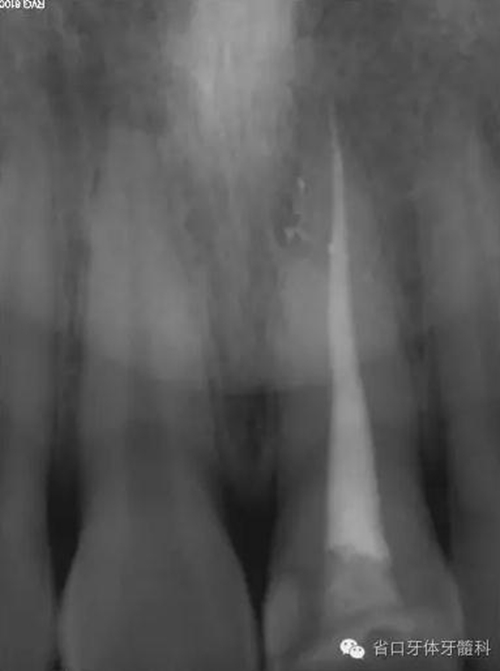

術(shù)前X線片

X線片示21冠折,根段未見(jiàn)明顯牙折影像。